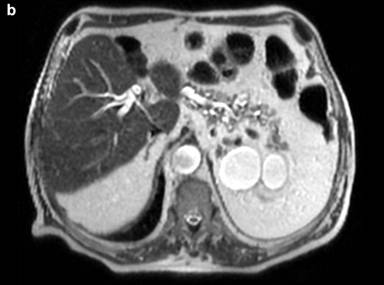

The medical history of the patient began when he was 60-year-old. Following the diagnosis of diabetes mellitus, an abdominal ultrasound (US), showed the incidental finding of a cystic lesion, 30 mm in diameter, located in the pancreatic head. Magnetic resonance imaging (MRI) and cholangiopancreatography showed a cystic lesion, 30 mm in diameter, without mural nodules and communicating with a non-dilated main pancreatic duct. Ultrasound-guided fine needle aspiration (FNA) of the cystic fluid showed high levels of CEA (104 ng/mL; normal value <5) and amylase (1230 U/L; normal value <70). Taking into account the age of the patient (having a long life-expectancy), the cystic size (30 mm) and the diagnosis of a branch-duct IPMN, the patient underwent surgery. At laparotomy, neither careful palpation of the gland or intra-operative ultrasound showed the cystic lesion. Thus, the surgery consisted of an exploratory laparotomy (April, 1999). The patient was enrolled in a surveillance program with yearly abdominal US scans. Five years after surgery, US showed a cystic lesion (diameter 17 mm) of the pancreatic head without mural nodules and Wirsung dilatation. Subsequent evaluations of the cystic lesion with US scans showed stable disease until April 2013, that is 14 years after the diagnosis and the exploratory laparotomy. At this time, the cystic lesion showed an increase in size (from 17 mm in diameter to 29 mm x 32 mm). Magnetic resonance imaging plus cholangio-pancreatography showed additional cystic enlargement (60 mm x 26 mm) and diffuse Wirsung duct dilatation (8 mm) (Figures 1 and 2). Finally, endoscopic ultrasound (EUS) confirmed a cystic lesion 3 cm in diameter communicating with a diffusely dilated main duct (maximum diameter 15 mm), revealing the presence of the “fish-eye” sign and several contrast-enhancing mural nodules inside the cyst. Endoscopic ultrasound FNA did not show malignant cells. Taking into consideration the presence of these “high-risk-stigmata” according to the Fukuoka guidelines [3], the patient underwent surgery; a total pancreatectomy was performed due to the involvement of the entire pancreatic gland. Pathological examination revealed a mixed-IPMN diffused throughout the entire pancreas with high grade dysplasia, and a micro-invasive carcinoma (<1 mm) of the pancreatic head. The postoperative course was uneventful and the patient was discharged on postoperative day 12. At six months from surgery, the patient is alive and well, without recurrences.

Figure 1. Fourteen years after diagnosis, MRI plus cholangio-pancreatography showed a sudden increase in size (60 mm x 26 mm) of the cystic lesion in the pancreatic head and diffuse Wirsung duct dilatation (8 mm). |